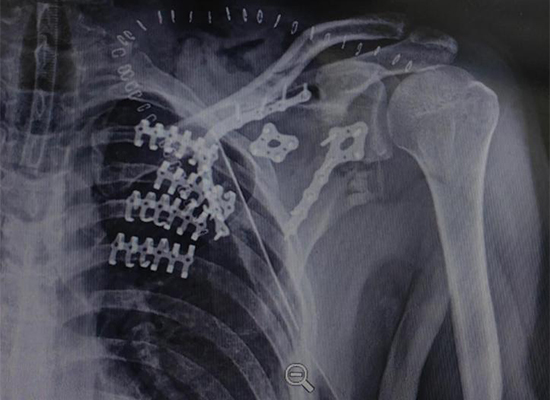

Предоперационная рентгенологическая оценка выявила множественные переломы ребер со смещением, признаки которых соответствовали нестабильности грудной клетки. Нарушение непрерывности ребер указывает на аномальные движения грудной клетки, увеличивая риск нарушения дыхания.

Результаты визуализации сыграли решающую роль в подтверждении тяжести травмы и поддержали решение об оперативном вмешательстве, а не о нехирургическом лечении.

Послеоперационная визуализация подтвердила стабильную фиксацию сегментов ребер и восстановление выравнивания грудной клетки. Грудная клетка продемонстрировала улучшенную структурную целостность без признаков смещения имплантата.

Фиксирующая конструкция обеспечивала достаточную стабильность для поддержки послеоперационной дыхательной функции и протоколов реабилитации.

Результат операции продемонстрировал восстановление анатомического выравнивания и функциональной стабильности грудной стенки, что подтверждает эффективность хирургической стабилизации грудной клетки в данном случае травмы. Проверка изображений и клиническое улучшение указали на успешное вмешательство.